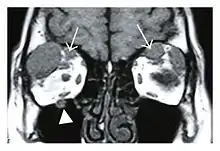

![]() Swelling of the left superior and lateral rectus muscles, a mass lesion around the left optic disc (arrow), and enlargements of the left supraorbital nerve and the right infraorbital nerve (arrow heads) in a 60-year-old man with a serum IgG4 of 463 mg/dL.[1] (T1-weighted MRI) |